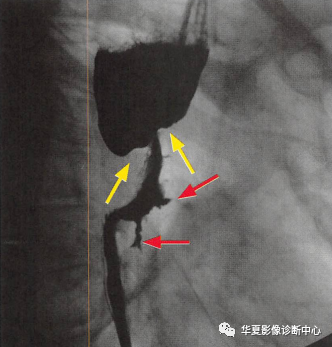

食管癌在鋇餐造影下的一種表現之一,顯示食管局部不規則狹窄(黃箭頭:玫瑰花花干),近端食管擴張(萎陷的玫瑰花朵),兩個不規則線狀潰瘍(紅箭頭:玫瑰花葉/刺),形似黑色玫瑰花,小編原創命名為:“黑色玫瑰花征”,幫助記憶,加深映像

進展期食管癌的典型表現為腫塊所致狹窄,伴有“肩胛征”和不規整輪廓。較少見的串珠樣表現可與靜脈曲張混淆,但腫瘤并不會因蠕動波而改變形狀,而靜脈曲張則都有改變。

為食管癌最典型X線表現。局部黏膜皺襞中斷、破壞、甚至消失,腔內錐形、半月形或不規則形龕影和充盈缺損,病變管壁顯示僵硬和蠕動消失。各型主要表現如下:

③潰瘍型:顯示為大小和形態不同的腔內龕影,邊緣不光整,部分龕影底部超出食管輪廓。潰瘍沿食管長軸破潰伴邊緣隆起時,出現“半月征”,周圍繞以不規則環堤。